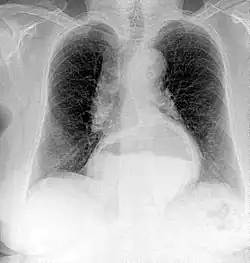

A chest radiograph of a female patient, demonstrating a hiatal hernia

Since Röntgen's discovery that X-rays can identify bone structures, X-rays have been used for medical imaging.[112] The first medical use was less than a month after his paper on the subject.[39] Up to 2010, five billion medical imaging examinations had been conducted worldwide.[113] Radiation exposure from medical imaging in 2006 made up about 50% of total ionizing radiation exposure in the United States.[114]

Projectional radiography is the practice of producing two-dimensional images using X-ray radiation. Bones contain a high concentration of calcium, which, due to its relatively high atomic number, absorbs X-rays efficiently. This reduces the amount of X-rays reaching the detector in the shadow of the bones, making them clearly visible on the radiograph. The lungs and trapped gas also show up clearly because of lower absorption compared to tissue, while differences between tissue types are harder to see.[115]

Projectional radiographs are useful in the detection of pathology of the skeletal system as well as for detecting some disease processes in soft tissue. Some notable examples are the very common chest X-ray, which can be used to identify lung diseases such as pneumonia, lung cancer, or pulmonary edema, and the abdominal x-ray, which can detect bowel (or intestinal) obstruction, free air (from visceral perforations), and free fluid (in ascites). X-rays may also be used to detect pathology such as gallstones (which are rarely radiopaque) or kidney stones which are often (but not always) visible. Traditional plain X-rays are less useful in the imaging of soft tissues such as the brain or muscle. One area where projectional radiographs are used extensively is in evaluating how an orthopedic implant, such as a knee, hip or shoulder replacement, is situated in the body with respect to the surrounding bone. This can be assessed in two dimensions from plain radiographs, or it can be assessed in three dimensions if a technique called '2D to 3D registration' is used. This technique purportedly negates projection errors associated with evaluating implant position from plain radiographs.[116]